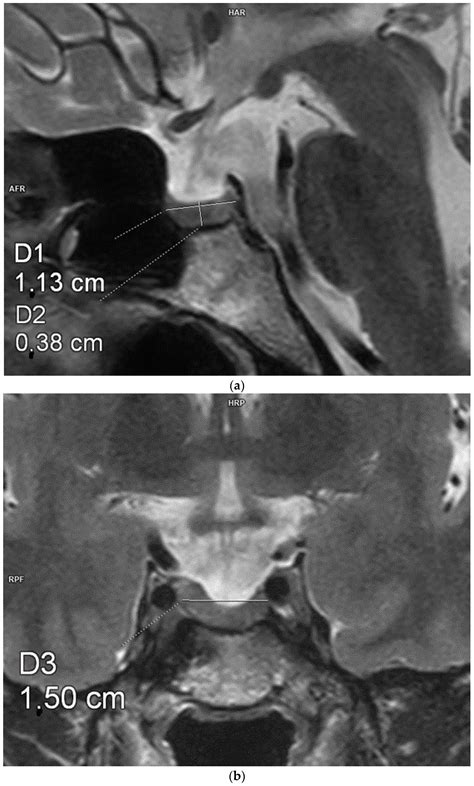

• Imaging Studies: Magnetic Resonance Imaging (MRI) is the gold standard for visualizing the pituitary gland and the sella turcica. It can show the extent of the empty sella and any associated abnormalities.

• partial empty sella mri

• partial empty sella radiology

• partial empty sella mri brain

• partial empty sella turcica